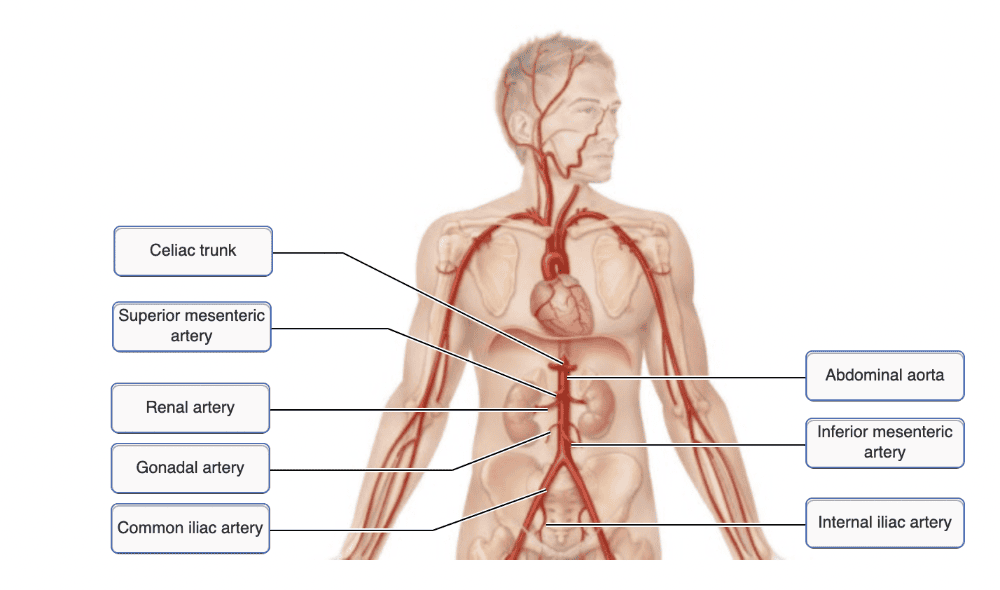

The branches of the abdominal aorta include all of the following except:

- superior mesenteric

- celiac trunk

- gonadal

- bronchial

bronchial